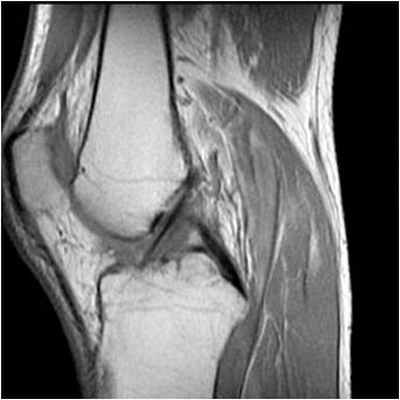

На снимке – разрыв крестообразной связки и мениска вследствие травмы колена

Для диагностики важна еще и форма мениска. В норме он в определенной плоскости имеет форму бабочки. Любые отклонения могут указывать на возможный разрыв.

Результаты. Чувствительность МРТ в диагностике разрывов менисков оказалось наиболее высокой и составила для латерального мениска 91,7% и для медиального мениска 95,4%. В то же время при диагностике разрывов передней крестообразной связки, МРТ-исследование не обладает столь высокой чувствительностью (88,2%). Кроме вышеописанных признаков, МРТ дает возможность определения повреждений костных и хрящевых структур. Также по данным МРТ можно определить план хирургического вмешательства при разрывах менисков и крестообразных связок.